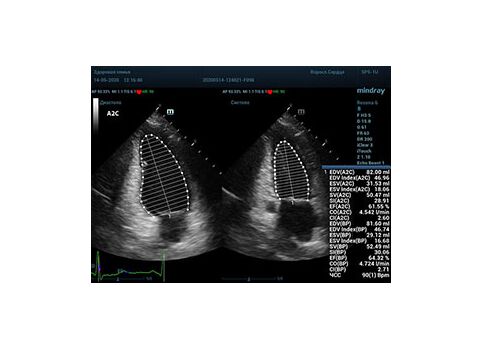

С появлением В режима реализовалась возможность визуализации всех сегментов миокарда из парастернальных и апикальных сечений. Метод Teicholtz в широкой практике сменился методом дисков. Метод дисков, или метод Simpson, позволяет разбить левый желудочек на 20 дисков, с расчетом объема каждого из них. Используя 2 перпендикулярных сечения, апикальные двух и четырех камерное, мы приближаемся к значению реального объема левого желудочка. Исследователь обводит интерфейс эндокард – кровь в фазу диастолы и фазу систолы. Линия простирается от кольца митрального клапана и до кольца митрального клапана, четко разграничивая объем желудочка от предсердия. Для достоверного изменения необходимо использовать ЭКГ канал.

Обводить вручную эти линии занимало много времени, однако результат того стоил. Следующим шагом стало появление Spline технологии, позволяющее расставлять точки и автоматически их соединять. Такой способ планиметрии контура эндокарда значительно сократил время измерения.

Что могут предложить современные приборы? Приборы нашего времени являются мощными вычислительными машинами, способными обрабатывать полученную информацию даже без помощи человека. Система автоматического вычисления фракции выброса – AUTO EF на приборах серии Resona компании Mindray сделает все за вас. За пару секунд прибор сам отыщет нужную фазу сердечного цикла и произведёт измерение и расчеты, а также покажет график изменения объема в сердечном цикле. От Вас требуется только получить качественное 4С и 2С сечение. Впрочем, прибор всегда оставляет возможность коррекции, если доктор имеет свое мнение на расположение точек планиметрии или момента измерения по ЭКГ каналу.